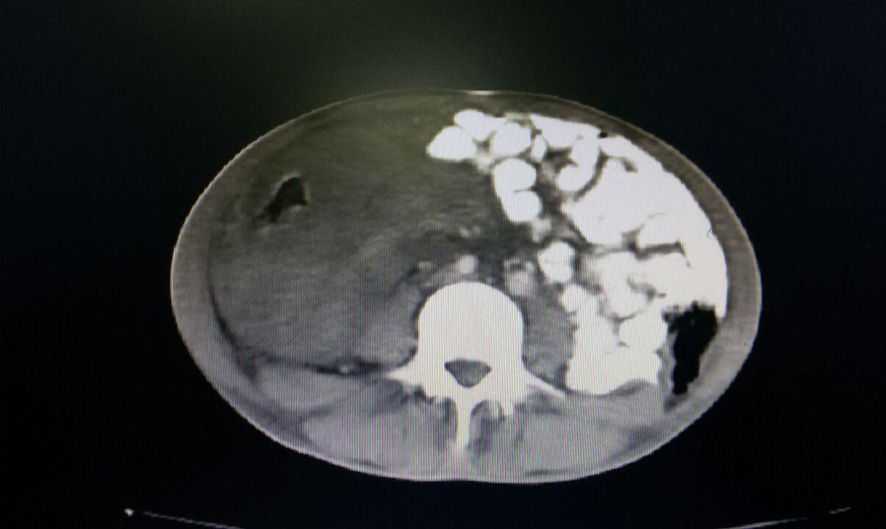

In the CT scan, mild left-sided pleural effusion was noted, but increased thickness of the abdominal wall and irregularities in the wall of the small intestine, particularly in the terminal ileum, were evident. An enhancing soft tissue mass was observed on the side (Figure-1). The rightward displacement of the small intestine to the left side of the abdominal cavity was reported, along with free fluid in the abdomen and pelvis. (Figure-2).

Figure 1. A CT scan of the patient before surgery indicated the size of the mass and the extent of abdominal involvement.

Figure 2. A CT scan of the patient before surgery indicated the size of the mass and the extent of abdominal involvement.